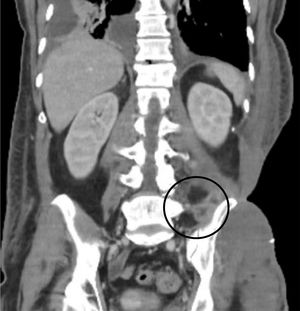

The patient initially made poor progress; the flank necrosis continued to spread, and the he developed septic shock, requiring administration of vasoactive agents and invasive mechanical ventilation. A computed tomography (CT) scan showed signs of severe myositis affecting the muscles of the left flank and gluteus.

One month after admission and after achieving negative cultures, coverage of the defect was begun with meshed partial autologous skin grafts, with successful results (Fig. 4). In total, Plastic Surgery performed six debridement operations and two coverage operations. After 50 days in the Intensive Care Unit, the patient was well enough to be transferred to a conventional hospital ward. After stabilisation of the cutaneous and subcutaneous areas, persistent collections underlying the left iliac blade were identified, which behaved like abscesses on CT (Fig. 5). Ultrasound-guided drainage was impossible due to the de-epithelialised condition of the area, which contraindicated percutaneous access. Imaging tests were contradictory; a labelled leucocyte scintigraphy scan did not suggest active infection, but magnetic resonance imaging (MRI) was compatible with soft tissue abscesses in the left quadratus lumborum muscle, iliolumbar ligament and iliacus muscle, with signs of osteomyelitis in the sacrum and iliac bone. It was therefore decided to prescribe a prolonged course of oral posaconazole (300 mg/day). The patient was discharged on day 66 after admission. The treatment with posaconazole was extended for six months, without the patient developing any adverse effects. After this time, repeat MRI showed marked radiological improvement, with a decrease in the collections in the muscles adjacent to the left sacroiliac joint and no conclusive signs of osteomyelitis, so it was decided to stop the treatment. Three months after discontinuing the posaconazole, the patient is asymptomatic, with the skin coverage defect resolved and no signs of recurrence of the infection (Fig. 4).